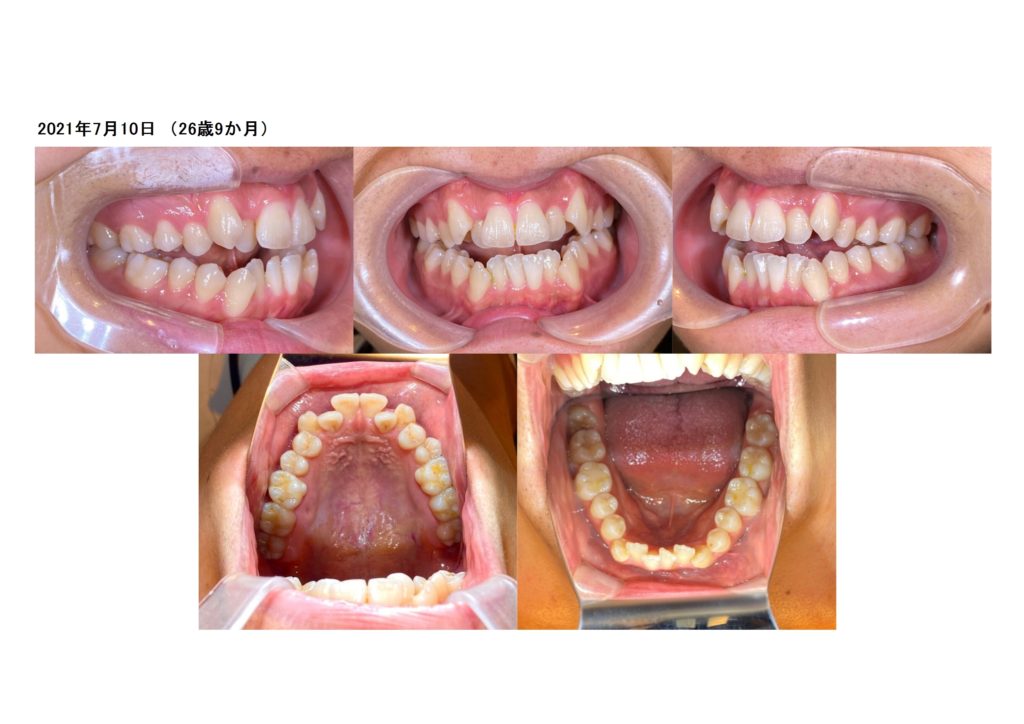

毎日意識してご自宅でトレーニングをしている方は1から2カ月もたてば噛み合わせが本当に改善してきます。

しっかりとご自宅でトレーニングをしてくれた方

「舌がもげそうになるかと思った。。。。」と。

でも、そのくらいしっかりと舌の筋トレしていただくととっても早く治療を終えることが出来ます。